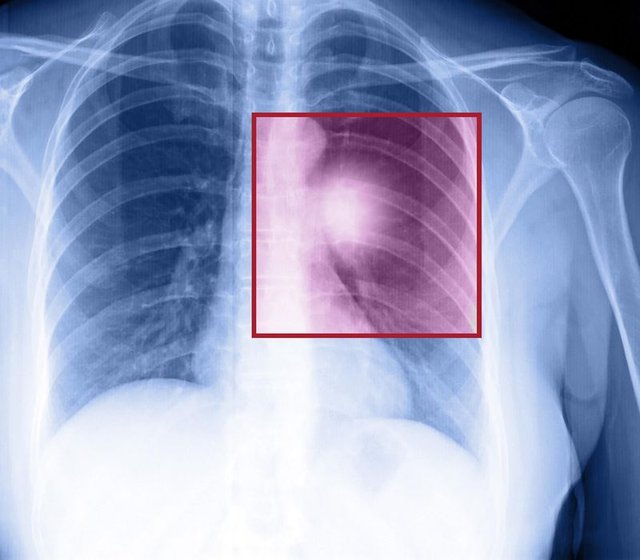

İleri evre akciğer kanseri hastaları maalesef ortalama 10-12 ay içinde hayatını kaybediyor.

1. Cerrahi: Eğer erken evrede yakalanıp ameliyatla akciğerdeki kanserli dokunun alınabildiği hastalar en şanslı hasta grubudur çünkü bu hastaların büyük bir kısmı 5 yıldan fazla yaşayabilir.

2. Radyasyon (ışın) tedavisi: Ameliyat öncesinde kanserli dokuyu küçültüp ameliyata uygun hale getirmek için kemoterapi (ilaç tedavisi) ile birlikte ışın tedavisi kullanılır.

3. Kemoterapi (ilaç tedavisi): Işın tedavisine benzer kullanım alanları mevcuttur. Ayrıca ileri evre kanser hastalarında ilk seçenek tedaviler arasındadır.

4. Hedefe yönelik tedaviler: Az miktarda sigara içmiş olan bazı hastalarda kemoterapi yerine kanser hücresindeki bir proteini hedef alan tablet şeklinde ilaçlar kullanılabiliyor ve bu hastaların çoğunda mucize denebilecek başarılar sağlanabiliyor.

Ayrıca son birkaç yıl içinde hastanın kendi bağışıklık sistemini kansere karşı aktifleştiren tedaviler de akciğer kanseri hastaları için ümit vadediyor.